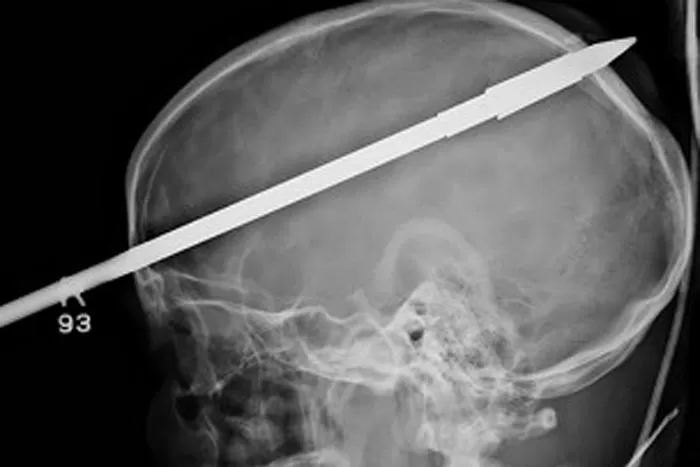

INCREIBLE. En esas condiciones llegó al hospital. FOTO TOMADA DE BBC.CO.UK

MIAMI, Estados Unidos.- Yasser López estaba pescando en Miami cuando, por error, se clavó un arpón de pesca en la cabeza que le atravesó el cerebro. Increíble pero cierto, el joven de 16 años sobrevivió al accidente y fue trasladado inmediatamente a un hospital de Miami, donde llegó consciente y tranquilo, según publica el medio inglés Daily Mail. Una vez internado, lo primero que hicieron los profesionales fue cortarle parte de la lanza para poder hacerle radiografías. La operación para extraerle la punta del arpón duró tres horas pero, afortunadamente, fue un éxito. Yasser, que tenía el arpón incrustado a la altura del ojo derecho y atravesando su cerebro, ya ha empezado a hablar y se está recuperando bien. (Especial)